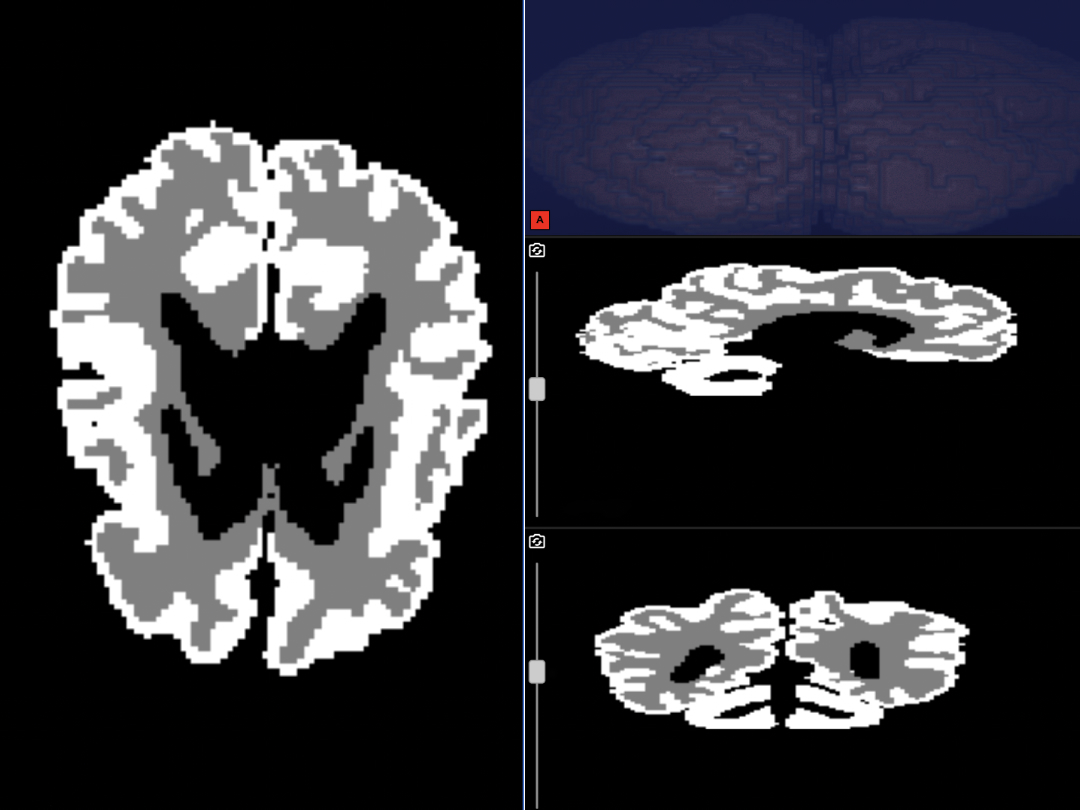

Нейросеть анализирует снимки и с точностью свыше 90% выделяет серое и белое вещество, показывая соотношение и состояние структур мозга. Для врача это — шанс быстрее поставить диагноз и выбрать тактику терапии. Обычно на расшифровку МРТ уходит от нескольких часов до нескольких дней, но теперь достаточно пары минут.

Решение развернули на платформе Yandex Cloud. Врач загружает снимки на специальную страницу проекта, данные анонимизируются автоматически — имя и личная информация пациента скрываются. На выходе получается готовое изображение с разметкой.